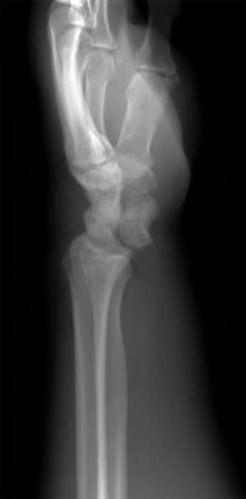

A 35-year-old woman reports wrist pain after a fall onto an outstretched hand. On exam, she has focal tenderness over the wrist snuffbox. A radiograph and CT image are shown in Figures A and B. What is the proper treatment of her injury?